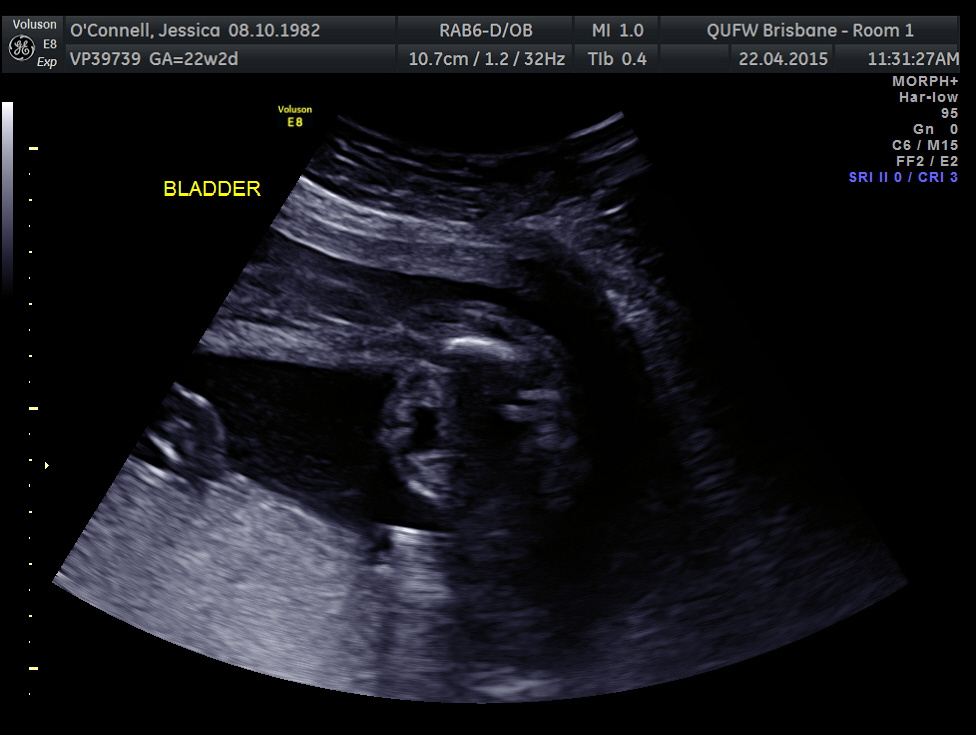

Attachment 24888Attachment 24889

2 more images. This is all I have